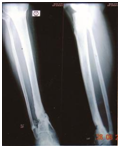

Figure 1 Case 1-Illustration.

1. Radiograph of 4 months old infected bone loss of right tibia fibula.

2. 55 years old male with uniaxial fixator in situ (right leg).

3. Radiograph of left tibia fibula 4 months old bimalleolar fracture.

4. Ilizarov apparatus in both legs.

5. During treatment right side.

6. Final radiograph of right tibia fibula.

7. Final radiograph of left bimalleolar fracture.

8. Final clinical appearance of the patient after 7 months.